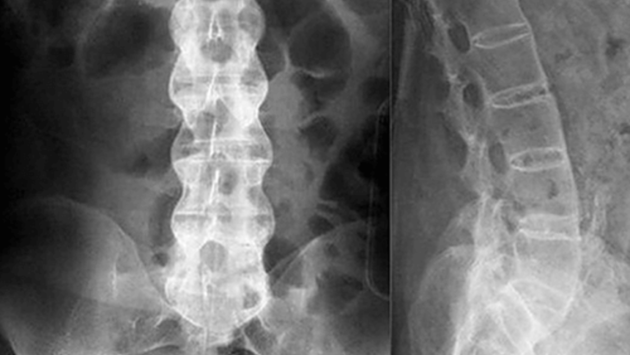

В России разработали новый эффективный препарат против болезни Бехтерева. В беседе с  РИА Новости академик Сергей Лукьянов напомнил, что при этой болезни у человека происходит окостенение позвоночника и различных суставов. Из-за этого больной теряет подвижность, постоянно испытывает боль.